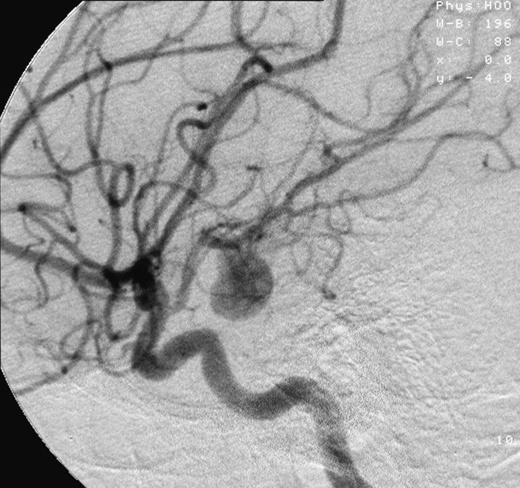

Aneurisma

Un aneurisma és una dilatació localitzada en un vas sanguini (artèria o vena) causada per una degeneració o afebliment de la paret vascular (vegeu la figura). Els aneurismes més freqüents són els arterials, i llur localització més habitual és a la base del cervell i a l’aorta (la principal artèria que surt del cor).